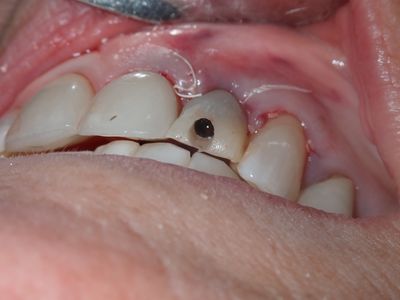

Atraumatic exo, loss of labial plate mid root about 2-3mm, CEJ and apical bone intact, region of thinner Labial-palatal bone, flapped site. osteotomy underprepared, implant placed with excellent stability. Buccal and socket grafted with 90/10 mix of mineralized cortical/xenograft followed by collagen membrane outside of socket on buccal, implant loaded with temporary crown out of centric and protrusive occlusion